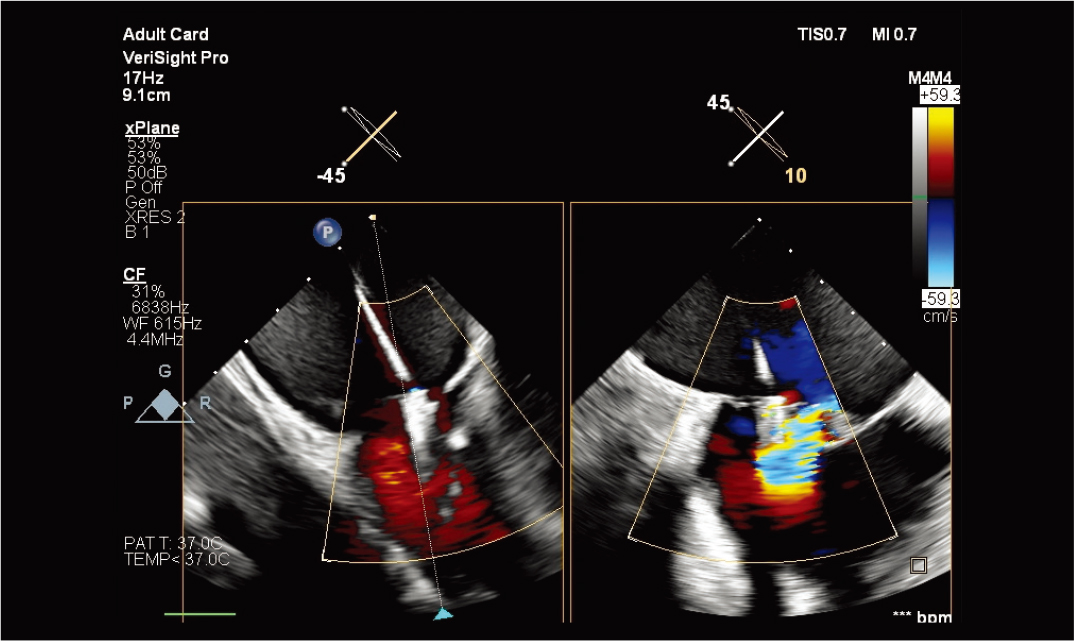

VeriSight Pro 3D ICE图像增强

改进的 3D 色彩支持介入手术的卓越性。

使用 VeriSight Pro 进行 xPlane 成像 |